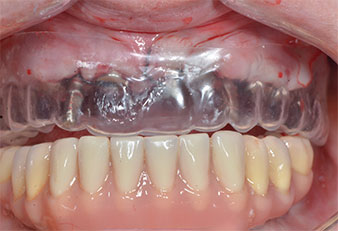

Gabarit en plastique

Fig. 9 : Un gabarit en plastique révèle qu'il y a suffisamment de place pour que la prothèse existante serve de prothèse temporaire fixée sur les implants provisoires.